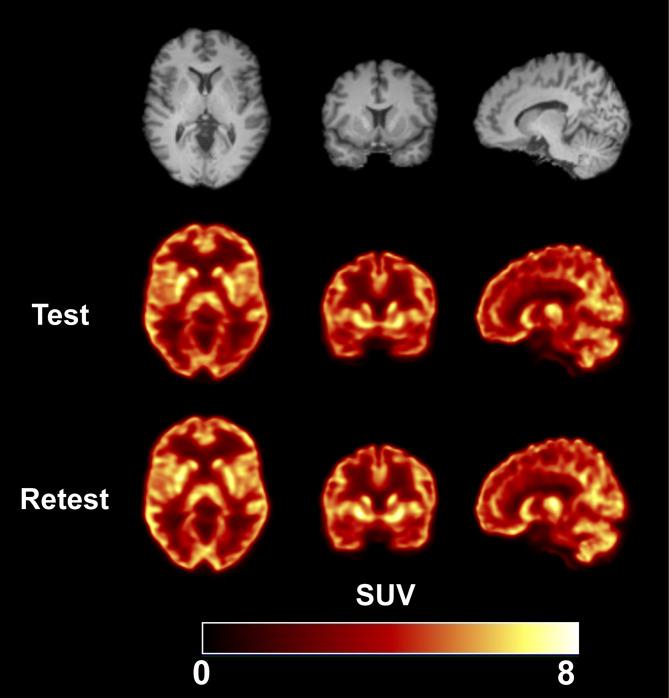

Assessment of test-retest reproducibility by [F]Bavarostat for PET imaging of HDAC6.

Six participants (3 M/3F) underwent a test-retest scan, each lasting for 120 min using a 4-ring Biograph mCT PET/CT scanner. Arterial blood sampling and metabolite analysis were performed to derive the input function. The two scans were 28 ± 12 days apart (14-43 days, n = 6). Regional time-activity curves (TACs) were generated for 15 regions of interest (ROIs). Kinetic analysis of the 120-min TACs was performed using one-tissue and two-tissue compartment models (1TC, 2TC) and multilinear analysis-1 (MA1) to quantify V values and compute absolute test-retest variability (aTRV). The effects of scan duration (60 to 120 min) and MA1 t* setting on aTRV and bias were investigated. Careful analysis of the plasma HPLC data was needed since metabolites eluted close in time to the parent. The MA1 model (t* = 40 min) adequately described regional TACs and produced stable kinetic parameters with good agreement to 2TC (MA1 V=0.98 × 2TC V + 0.48, bias: -0.1%) while 1TC underestimated V by 5.1%. Regional V values exhibited a relatively uniform pattern, highest in the amygdala and lowest in the centrum semiovale. Individual aTRV values ranged from 2 to 9%. Scan durations between 100 and 120 min provided the most consistent results, with minimal bias and acceptable aTRV across all tested t* values. Although a 90-minute scan with t*=10 or 20-minute balanced scan time and aTRV, optimal parameters varied by brain region. Smaller regions (e.g., amygdala) required longer scans to achieve reliable V quantification.

The test-retest variability of [F]Bavarostat V values demonstrated favorable results for a one-month scan interval, comparable to the reported values.